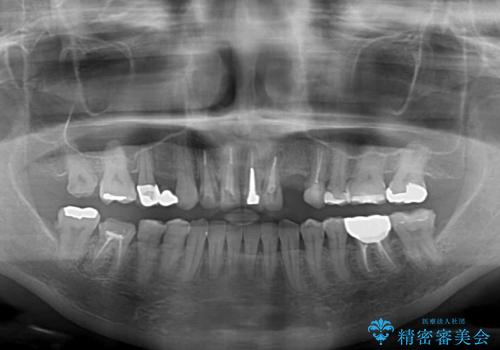

- 他院で矯正治療を終えたものの、むし歯や欠損部の治療が進められないとのことで来院された患者様です。

欠損部や、銀歯やむし歯の大きな歯はセラミッククラウンやブリッジに、小さいむし歯はセラミックインレーにて治療を行うこととしました。

歯肉の状態がとても、短期間でスムーズに治療を終えることができました。